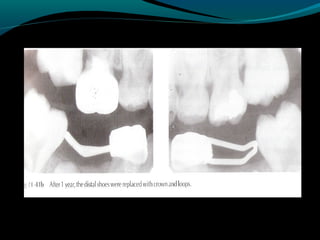

DISTAL SHOE

(Intra-alveolar,Eruption guidance

appliance)

o Used to maintain the space of a primary

second molar that has been lost before

the eruption of the permanent first

molar.

o An unerupted permanent first molar

drifts mesially within the alveolar bone if

the primary second molar is lost

prematurely.The result of the mesial

drifts is loss of arch length & possible

impaction of the second premolar.

DISTAL SHOE (Intra-alveolar,Eruption guidance appliance) oUsed to maintain the space of a primary second molar that has been lost before the eruption of the permanent first molar. o An unerupted permanent first molar drifts mesially within the alveolar bone if the primary second molar is lost prematurely.The result of the mesial drifts is loss of arch length & possible impaction of the second premolar.

• 54.